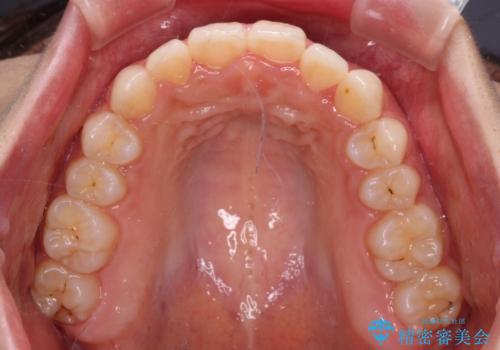

【モニター】前歯のクロスバイトをインビザラインで治療

- 前歯のデコボコとクロスバイトを気にして来院された患者様です。

上顎側切歯(上の真ん中から2番目の歯)が舌側転位している場合、インビザラインでは仕上げきれないことが多く、更には無理して動かそうとすると歯髄壊死を起こすリスクが高いと言われています。

今回は、ワイヤー装置を併用することなく、インビザライン単体で矯正治療を行うこととしました。

インビザライン特有の、奥歯の咬み合わせの問題もなく、しっかりと歯列を改善することができました。

舌側転位している上顎側切歯(内側に引っ込んでいる真ん中から2番目の歯)は、インビザラインが最も移動を苦手とする歯であり、これ以上の改善を望まれる場合にはワイヤー矯正、あるいはワイヤー矯正の併用をお勧めいたします。